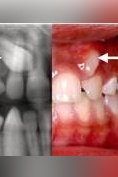

دندان اضافی

درمان مزیودنس یا دندان اضافی چیست؟

سوالات متداول در مورد دندان اضافی

چرا دندان اضافی درمیآوریم؟

علل ایجاد دندانهای اضافه چیست؟